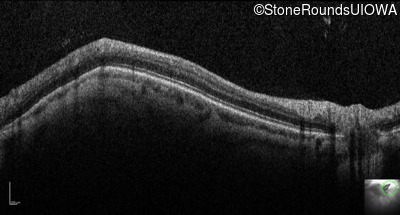

Optical Coherence Tomography - Left - 20/100

Exemplar